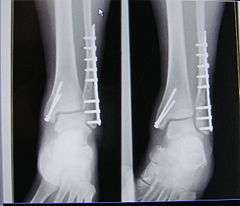

A trimalleolar fracture is a fracture of the ankle that involves the lateral malleolus, the medial malleolus, and the distal posterior aspect of the tibia, which can be termed the posterior malleolus. The trauma is sometimes accompanied by ligament damage and dislocation.[1]

Surgical repair utilizing open reduction and internal fixation is generally required, and because there is no lateral restraint of the foot, the ankle cannot bear any weight while the bone knits. This typically takes six weeks in an otherwise healthy person but can take as much as twelve weeks. Non-surgical treatment may sometimes be considered in cases where the patient has significant health problems or where the risk of surgery may be too great.[1]

- X-ray of a trimalleolar fracture - ucsf.edu.